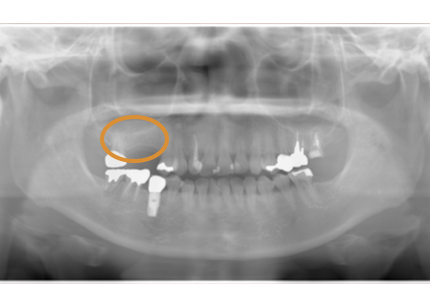

2.再生療法:エムドゲイン(2008年3月)

骨欠損部にエムドゲイン、バイオスを填入して、メンブレンにて閉鎖縫合する

8.再生療法術後16年 経過良好(2025年4月)